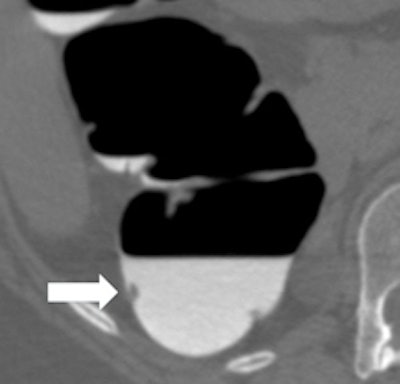

Left: Small 7-mm polyp in colon, drowned in tagged fluid in supine position (white arrow). Right: Corresponding 3D view in prone position shows the same polyp (white arrow). Images courtesy of Philippe Lefere, MD.Using a low dose may cause excess image noise, resulting in pseudoenhancement, but this problem can be solved by comparing the lesion with a tagged stool elsewhere in the colon, or by smoothing the abdominal window. When starting CTC as a novice, a dose of 80 mAs should be used to avoid image noise, he advised.